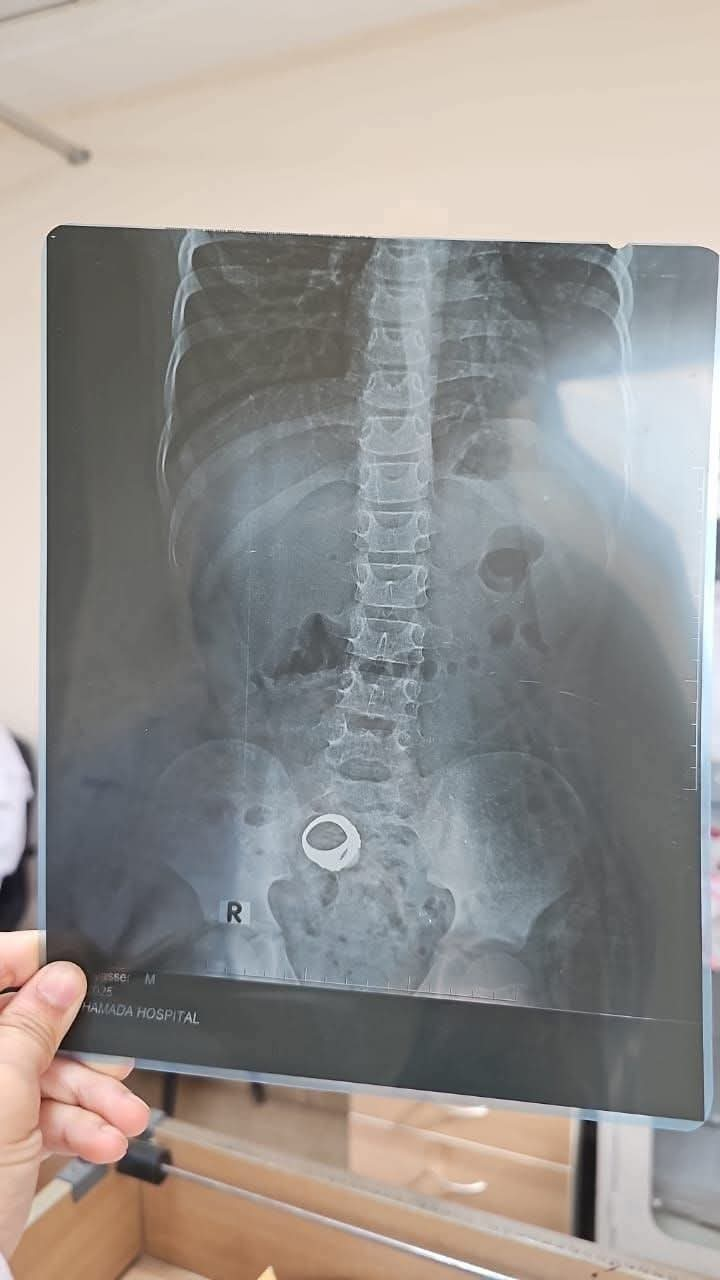

الخاتم المعندى يظهر فى الأشعة

وأصدرت إدارة مستشفى كوم حمادة العام بيانًا إعلاميًا عبر صفحتها على موقع فيس بوك بشأن حالة الطفل معاذ عمار، الذي دخل المستشفى مساء أمس الخميس، وكان يعاني من تلبك معوي نتيجة وجود خاتم معدني داخل بطنه.

وأكدت إدارة المستشفى أنه تم الكشف على الحالة، وأن والدة الطفل أجرت الأشعة اللازمة على منطقة البطن، لكنها غادرت قبل انتظار النتيجة، ولم تعد مرة أخرى للعيادة الخارجية لمتابعة الحالة الصحية للطفل.